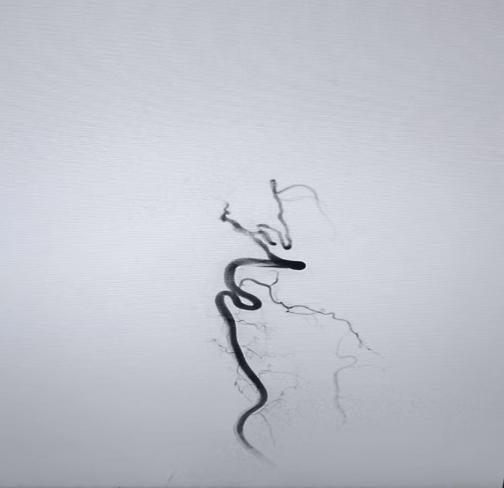

值班医生立即向神经内四科主任包瑛汇报病情,经评估,患者符合血管内介入治疗指征,需立即行基底动脉取栓术。在与患者家属充分沟通病情后,医院迅速启动导管室绿色通道。由包瑛带领的介入团队开展手术,术中造影证实患者基底动脉中段闭塞,且手术路径困难,患者还合并有多发动脉瘤,随时可能破裂。在介入团队的精湛操作和不懈努力下,成功为患者实施了基底动脉支架取栓及球囊扩张成形术,闭塞血管被成功开通,实现了血流再通。术后,患者被转入卒中单元进行严密监护,病情逐步稳定,为后续康复奠定基础。